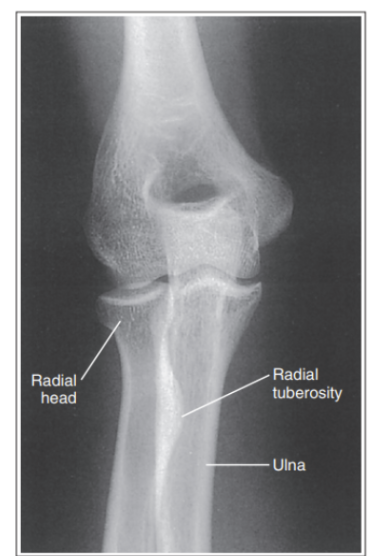

More than 1/8 of the radial head is superimposing with the ulna

Internal rotation

Less than 1/8 of the radial head is superimposing with the ulna

External rotation